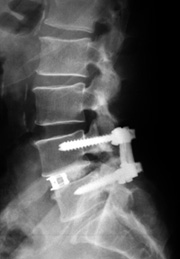

腰椎すべり症の手術(腰椎固定術)

除圧と固定を行う手術です。神経を圧迫している部分を切除した後、患者さん自身の骨(移植骨)や人工骨を挿入して固定します。さらにスクリューやプレート等を使用して脊椎の安定性を高める場合(インストゥルメンテーション)があります。

術後の経過

アプローチの方法、インストゥルメンテーションの有無、痛みの程度や患者さんの状態によって異なります。

通常、問題がなければ術後1~2日目からの歩行が目安になります。歩行器を用いて少しずつ歩行を開始します。術後7日目に抜糸し、術後2~3週間で退院となります。

簡単な仕事なら術後1ヶ月ごろから可能です。ただし、術後3ヶ月間は重労働や激しい運動は控えてください。

患者さんの状態によって異なりますが、一般的には、骨が完全につくまでの期間(術後およそ3月間)は腰椎の固定装具(コルセット)を装着します。